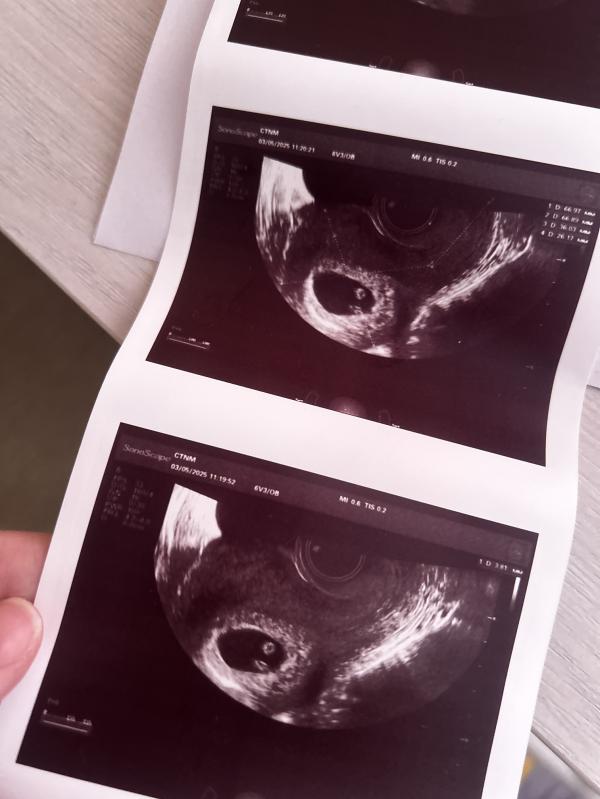

Все хорошо 🙏🏻 сердцебиение есть, так переживала…

У вас двойня?😍 легкой беременности 🙏🏻🤲🏻

Нет один) спасибо 😘